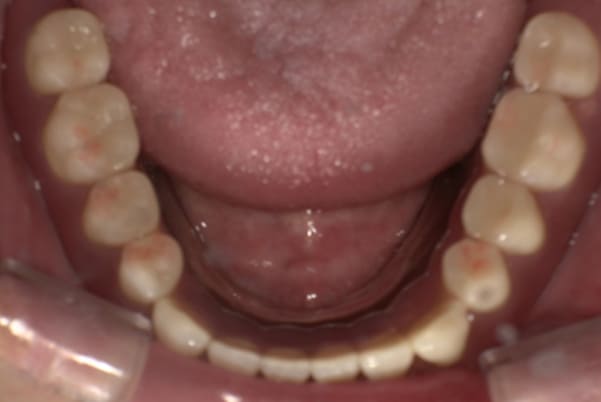

下顎治療前

-

下顎治療後

治療前の入れ歯の奥歯は、治療後の義歯と比較しても分かるように、歯が削れ平らになった状態です。

これにより奥歯のかみ合わせは低くなり、前歯のみが強くあたり、かみ合わせにより上の前歯大きな負担がかかっていたことにより、上の前歯が折れたことが考えられます。